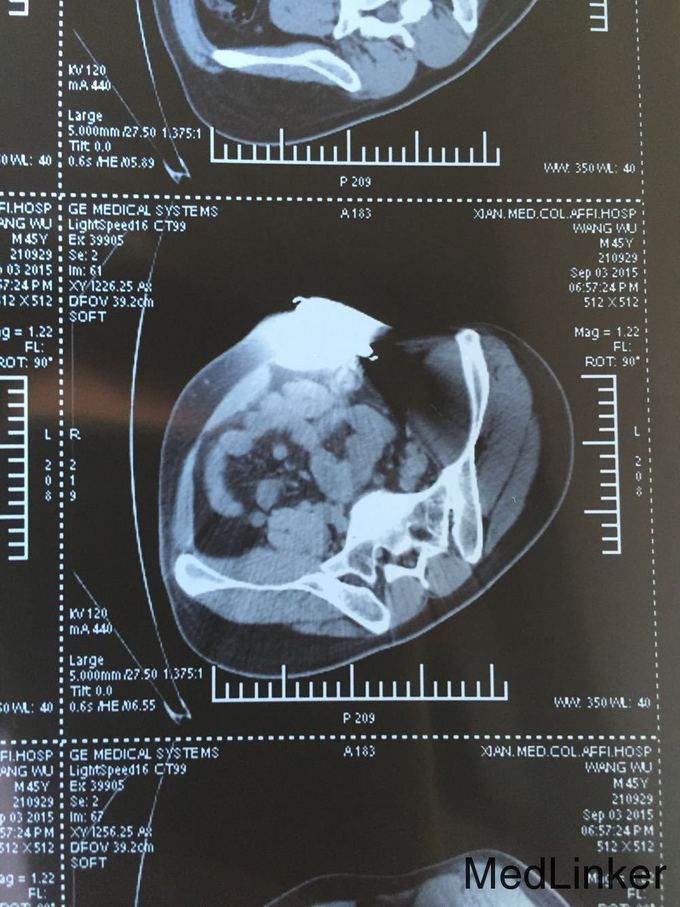

查体:T:36.6℃,P:80次/分,R:19次/分,Bp:130/85mmHg。心肺未见明显异常,腹平坦,无腹壁静脉曲张,腹部柔软,无压痛、反跳痛,腹部无包块,左侧腰髂部近左臀部可见钢筋样异物刺入直达左下腹腹壁皮下,未穿透腹壁皮肤,左臀部皮肤裂伤伴出血,伤口处压痛,肝脾肋下未触及,左下腹压痛,Murphy氏征阴性,移动性浊音阴性,肝脾肾区无叩击痛,肠鸣音未见异常。 辅助检查:全腹部CT检查示:1.盆腔见条状金属致密物,从左臀穿向前下腹部皮下,长约28cm;2.左侧腹膜周围见少许渗出性改变;3.左侧精索肿胀,其内气体影,左侧睾丸肿胀;4.左侧髂骨骨折。